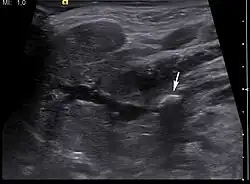

Diagnosis is usually made by characteristic history and physical examination. Diagnosis can be confirmed by x-ray (80% of salivary gland calculi are visible on x-ray), by sialogram, or by ultrasound.